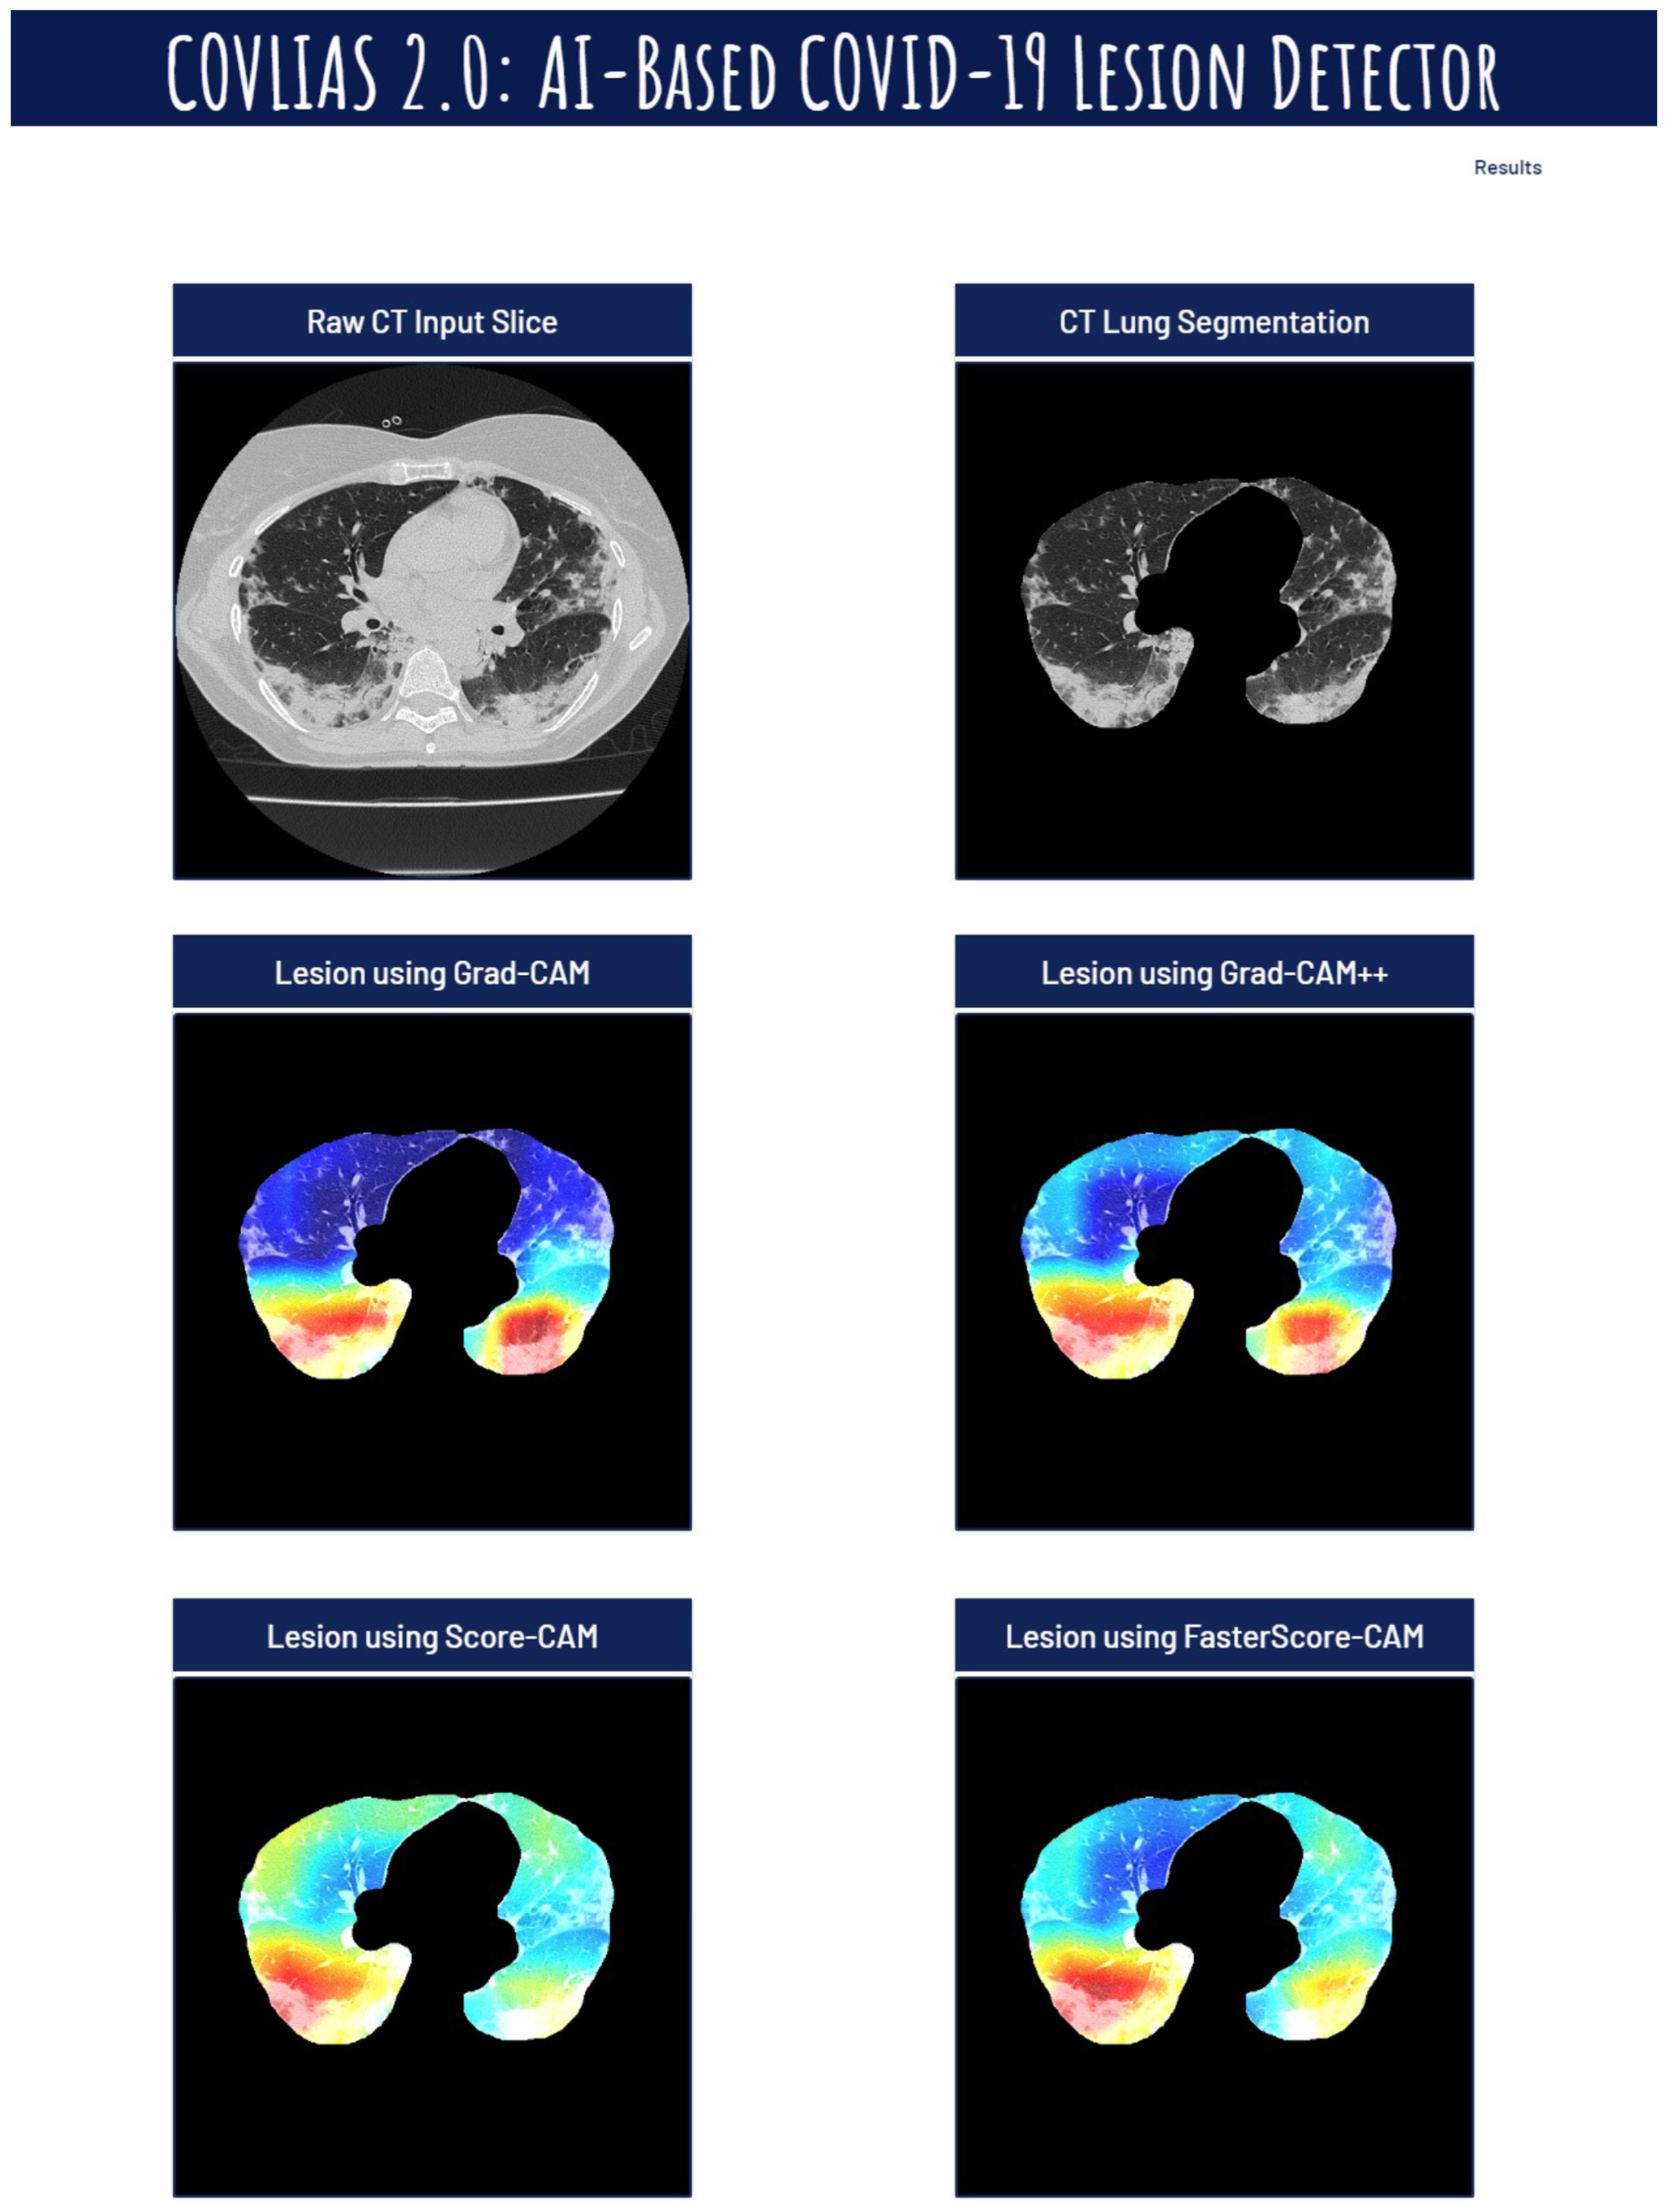

Visual Results Representing Lesion Using the Four CAM Techniques

4.1. Study Findings

4.4. A Special Note on Four CAM Models